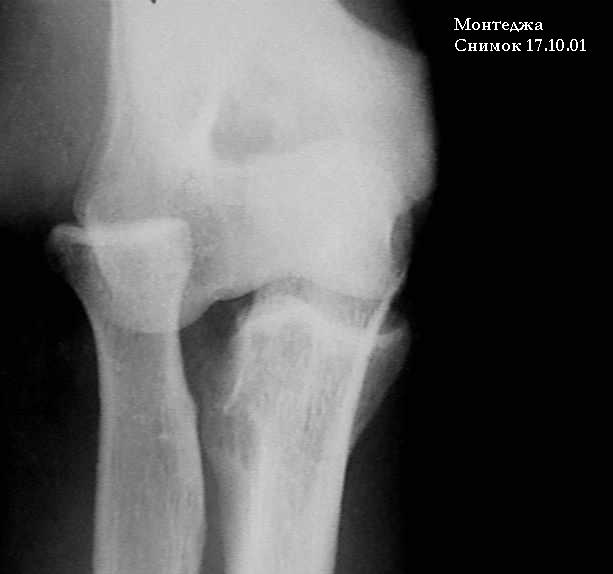

У больного травма в октябре 2001. Перелом Монтеджа разгибательный.Проведена операция металлостеосинтез пластиной, винтами локтевой кости. Вывих головки лучевой кости не диагностирован. В конце февраля 2002 г снята гипсовая повязка. Имеется ограничение сгибания до 115 градусов. Больной обратился в наше лечебное учреждение 07.02.02. Мы предложили ему оперативное лечение. Планируем провести резекцию головки лучевой кости. Есть мнение попытаться вправить головку лучевой кости, провести пластику кольцевидной связки, фиксисировать головку лучевой кости трансартикулярно спицей. Но боюсь, что в момент остеосинтеза была укорочена локтевая кость, поэтому необходимо будет провести резкцию в области диафиза лучевой кости, а затем провести остеосинтез лучевой кости. Рентгенограммы:

1; 2; 3; 4